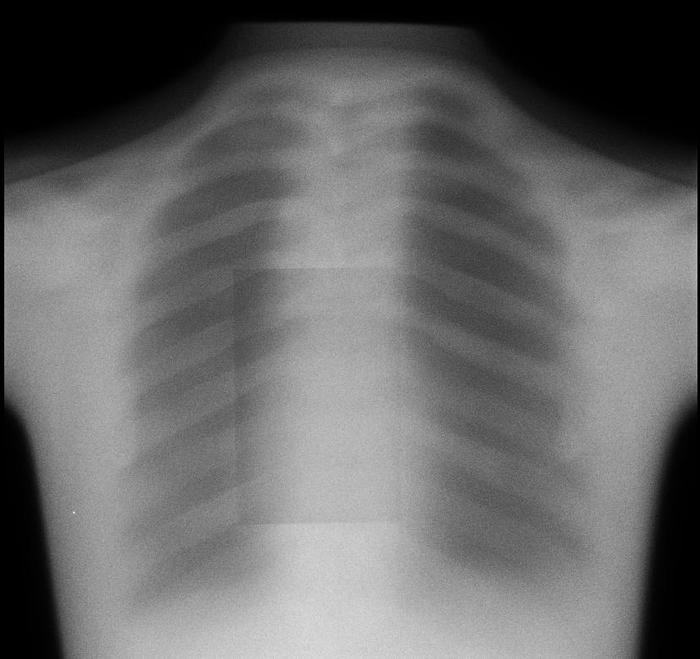

For both the lateral and the AP views, there are two separate sources of motion that could contribute to differences between the “pre” and “post” images: movement of the patient and the ovement of the spine and/or screws. The camera itself has preset positions for both views, with millimeter-level noise between separate images that can be effectively ignored. As the movements of the patient are extraneous, they introduce noise that makes it difficult to evaluate patient progress and diagnose any potential issues (e.g. pseudarthrosis) that may cause major health risks. As a result, a patient that may come in after their operation to diagnose why they haven’t seen the expected improvement may require additional x-rays which delay the process, which could result in any medical conditions worsening or potentially another operation being required.

We will create an algorithm enabling users to upload both the “pre” and “post” images, realign/manipulate them, and eliminate noise induced by movement of the patient. By doing so, the lab will be able to make more accurate diagnoses and prognoses of their patients. Having specific, quantitative data on the relative positions and movements of screws and vertebral bodies of interest would help patients to make the best of their own and the lab’s time and diagnose any complications earlier for better health and less cost to the patient.